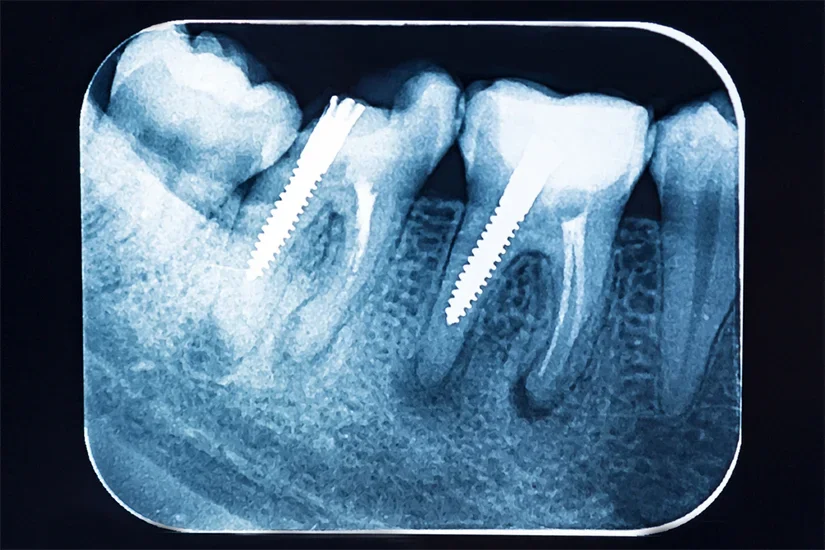

Radiografiile dentare sunt esențiale pentru a determina lungimea și integritatea rădăcinii dintelui. De asemenea, pot fi utilizate alte investigații imagistice, cum ar fi tomografia computerizată cu fascicul conic (CBCT), pentru a obține o imagine clară a structurii dentare și a rădăcinii. Astfel, un dinte pus cu pivot și coroană dentară va avea o structură similară dintelui original și nu va exercita forțe suplimentare asupra gingiei, maxilarului sau dinților adiacenți.